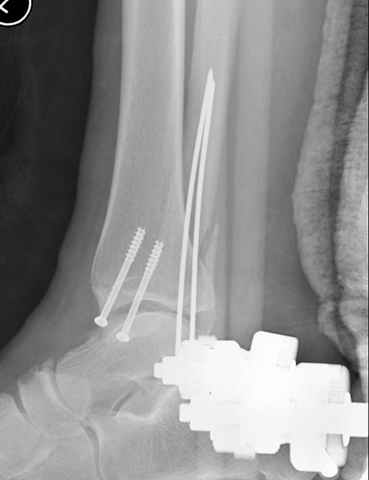

Второй случай сделан из одного разреза

Дж

ЕЧ LISS plate, mininvasive approach - luxurous !

Вопрос практического характера - такой подход рутинный или при определенных показаниях и каких? Спрашиваю потому, что при потоке больных - закрытая голень, бедро, голеностоп и т.д. лучевая нагрузка должна быть немалая, каковы показатели дозиметра после такого операционного дня и при 2-3 операционных днях в неделю по 5-6 случаев (не считая ургентностей)?

С точки зрения : Сгорая сам - свети другим :-)) это вполне понятно, но личная практика показывает, что далеко не все пациенты относятся волнительно и критично к длине кожного разреза. Подозреваю, что это и есть критерий при выборе техники фиксации?

На прямой проекции послеоперационного Рг макроскопически все выглядит очень анатомично, при микроскопическом ( :-)) ) рассмотрении можно все-таки заметить вальгизацию тарана, суставная щель в латеральном отделе сустава несколько уже , чем в медиальном при отсутствии латерального смещения тарана. У меня был аналогичный случай (без LISS , без мини доступа) с вальгусным наклоном тарана при восстановленном ankle mortise при последовательном наблюдении с интервалами в 6-8 недель в послеоперационном периоде отмечалось прогрессирующее сужение суставной щели в латеральном отделе сустава, закончившееся посттравматическим ОА, к счастью боли умеренные, купируемые аналгетиками или своими эндорфинами:-))(активная пациентка, у которой нет времени на болезни....) Какова жизненная ситуация в приведенном вами случае? И последнее, что я хотел бы прояснить для себя - фиксация внутренней лодыжки: я обычно комбинирую фиксацию компрессирующим винтом со спицей - по идее ротационная стабильность должна быть лучше, чем один винт, каковы ваши наблюдения в этом плане?